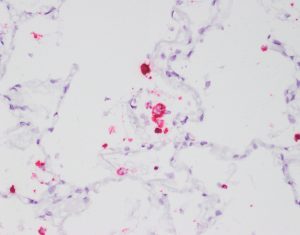

西尼罗河病毒是通过蚊子传播给人类的。虽然高达80%的感染者不会出现症状,但其余20%的人会出现脑炎的典型症状,如发烧、头痛、疲劳、不适、肌肉疼痛和虚弱。当病毒扩散到大脑时,会导致方向感障碍、运动障碍(严重震颤和帕金森病)、瘫痪,甚至昏迷和死亡。

当HIV-1进入大脑时,它靶向小胶质细胞,神经系统的哨兵免疫细胞。感染的小胶质细胞破坏了大脑并引起神经变性(神经元的渐进病)和痴呆。